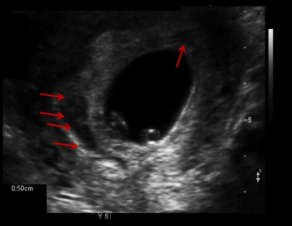

Subchorionic hemorrhage USA

Hypoechoic structure between chorion and UT wall

Usually crescent shaped

May see debris with thrombus formation within